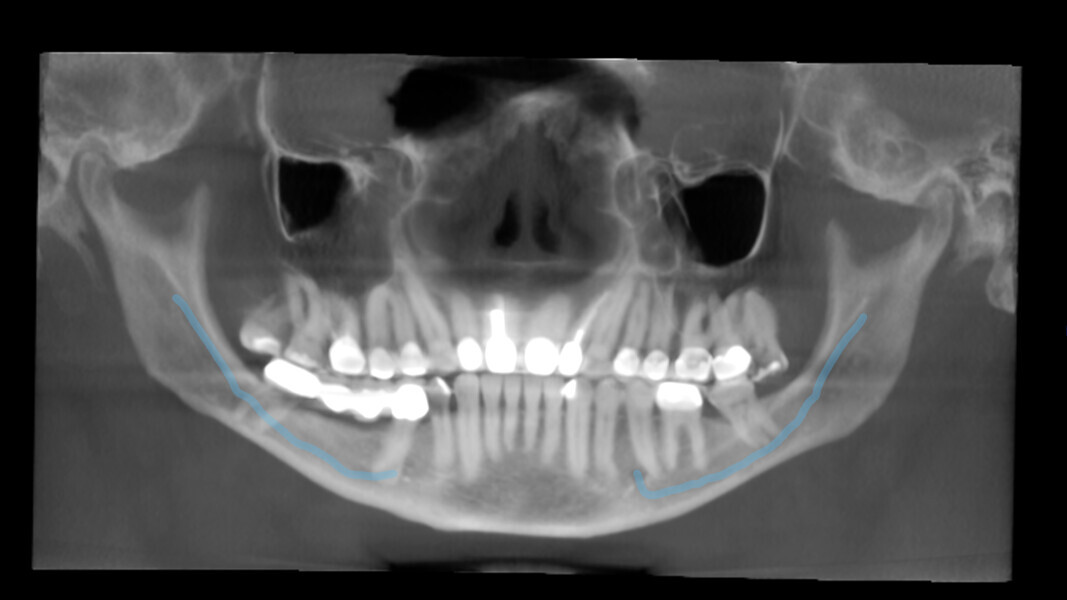

The third case highlights the artificial intelligence incorporated into DTX Studio Clinic, one feature of which is automatic tracing of the mandibular canal. In this case, it was a very helpful feature to have. The patient was suffering from irreversible pulpitis of a mandibular third molar. He wanted to save the tooth at any cost because did not want to have an implant (the molar was an abutment tooth for a bridge). The radiograph showed the roots of the molar overlapping the mandibular canal (Fig. 12). A 3D radiograph was taken, and on this, the software traced the mandibular canal overlapping the molar in the panoramic view. The endodontic mode revealed that the canal bypassed the buccal area, slightly touching the mesiobuccal canal (Figs. 13–15). The radiograph taken immediately after the root canal therapy, performed through the crown, showed complete obturation of all the canals (Fig. 16).